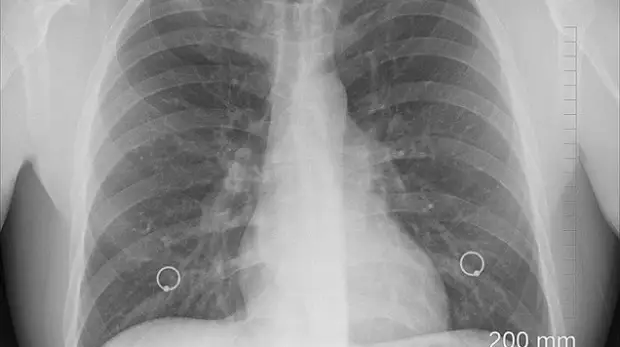

С 29 марта Филиал ФНКЦ ФМБА России в Крыму совместно с ГБУЗ РК «Крымский республиканский клинический центр фтизиатрии и пульмонологии» проведет акцию, посвященную борьбе с туберкулезом, профилактике и ранней диагностики этого опасного заболевания.

Об этом сообщили в пресс-службе филиала ФНКЦ ФМБА России в Крыму, передаёт корреспондент «Вести Крым». Специалисты отмечают, что в 2020 году от туберкулеза в Крым умерло 156 человек.